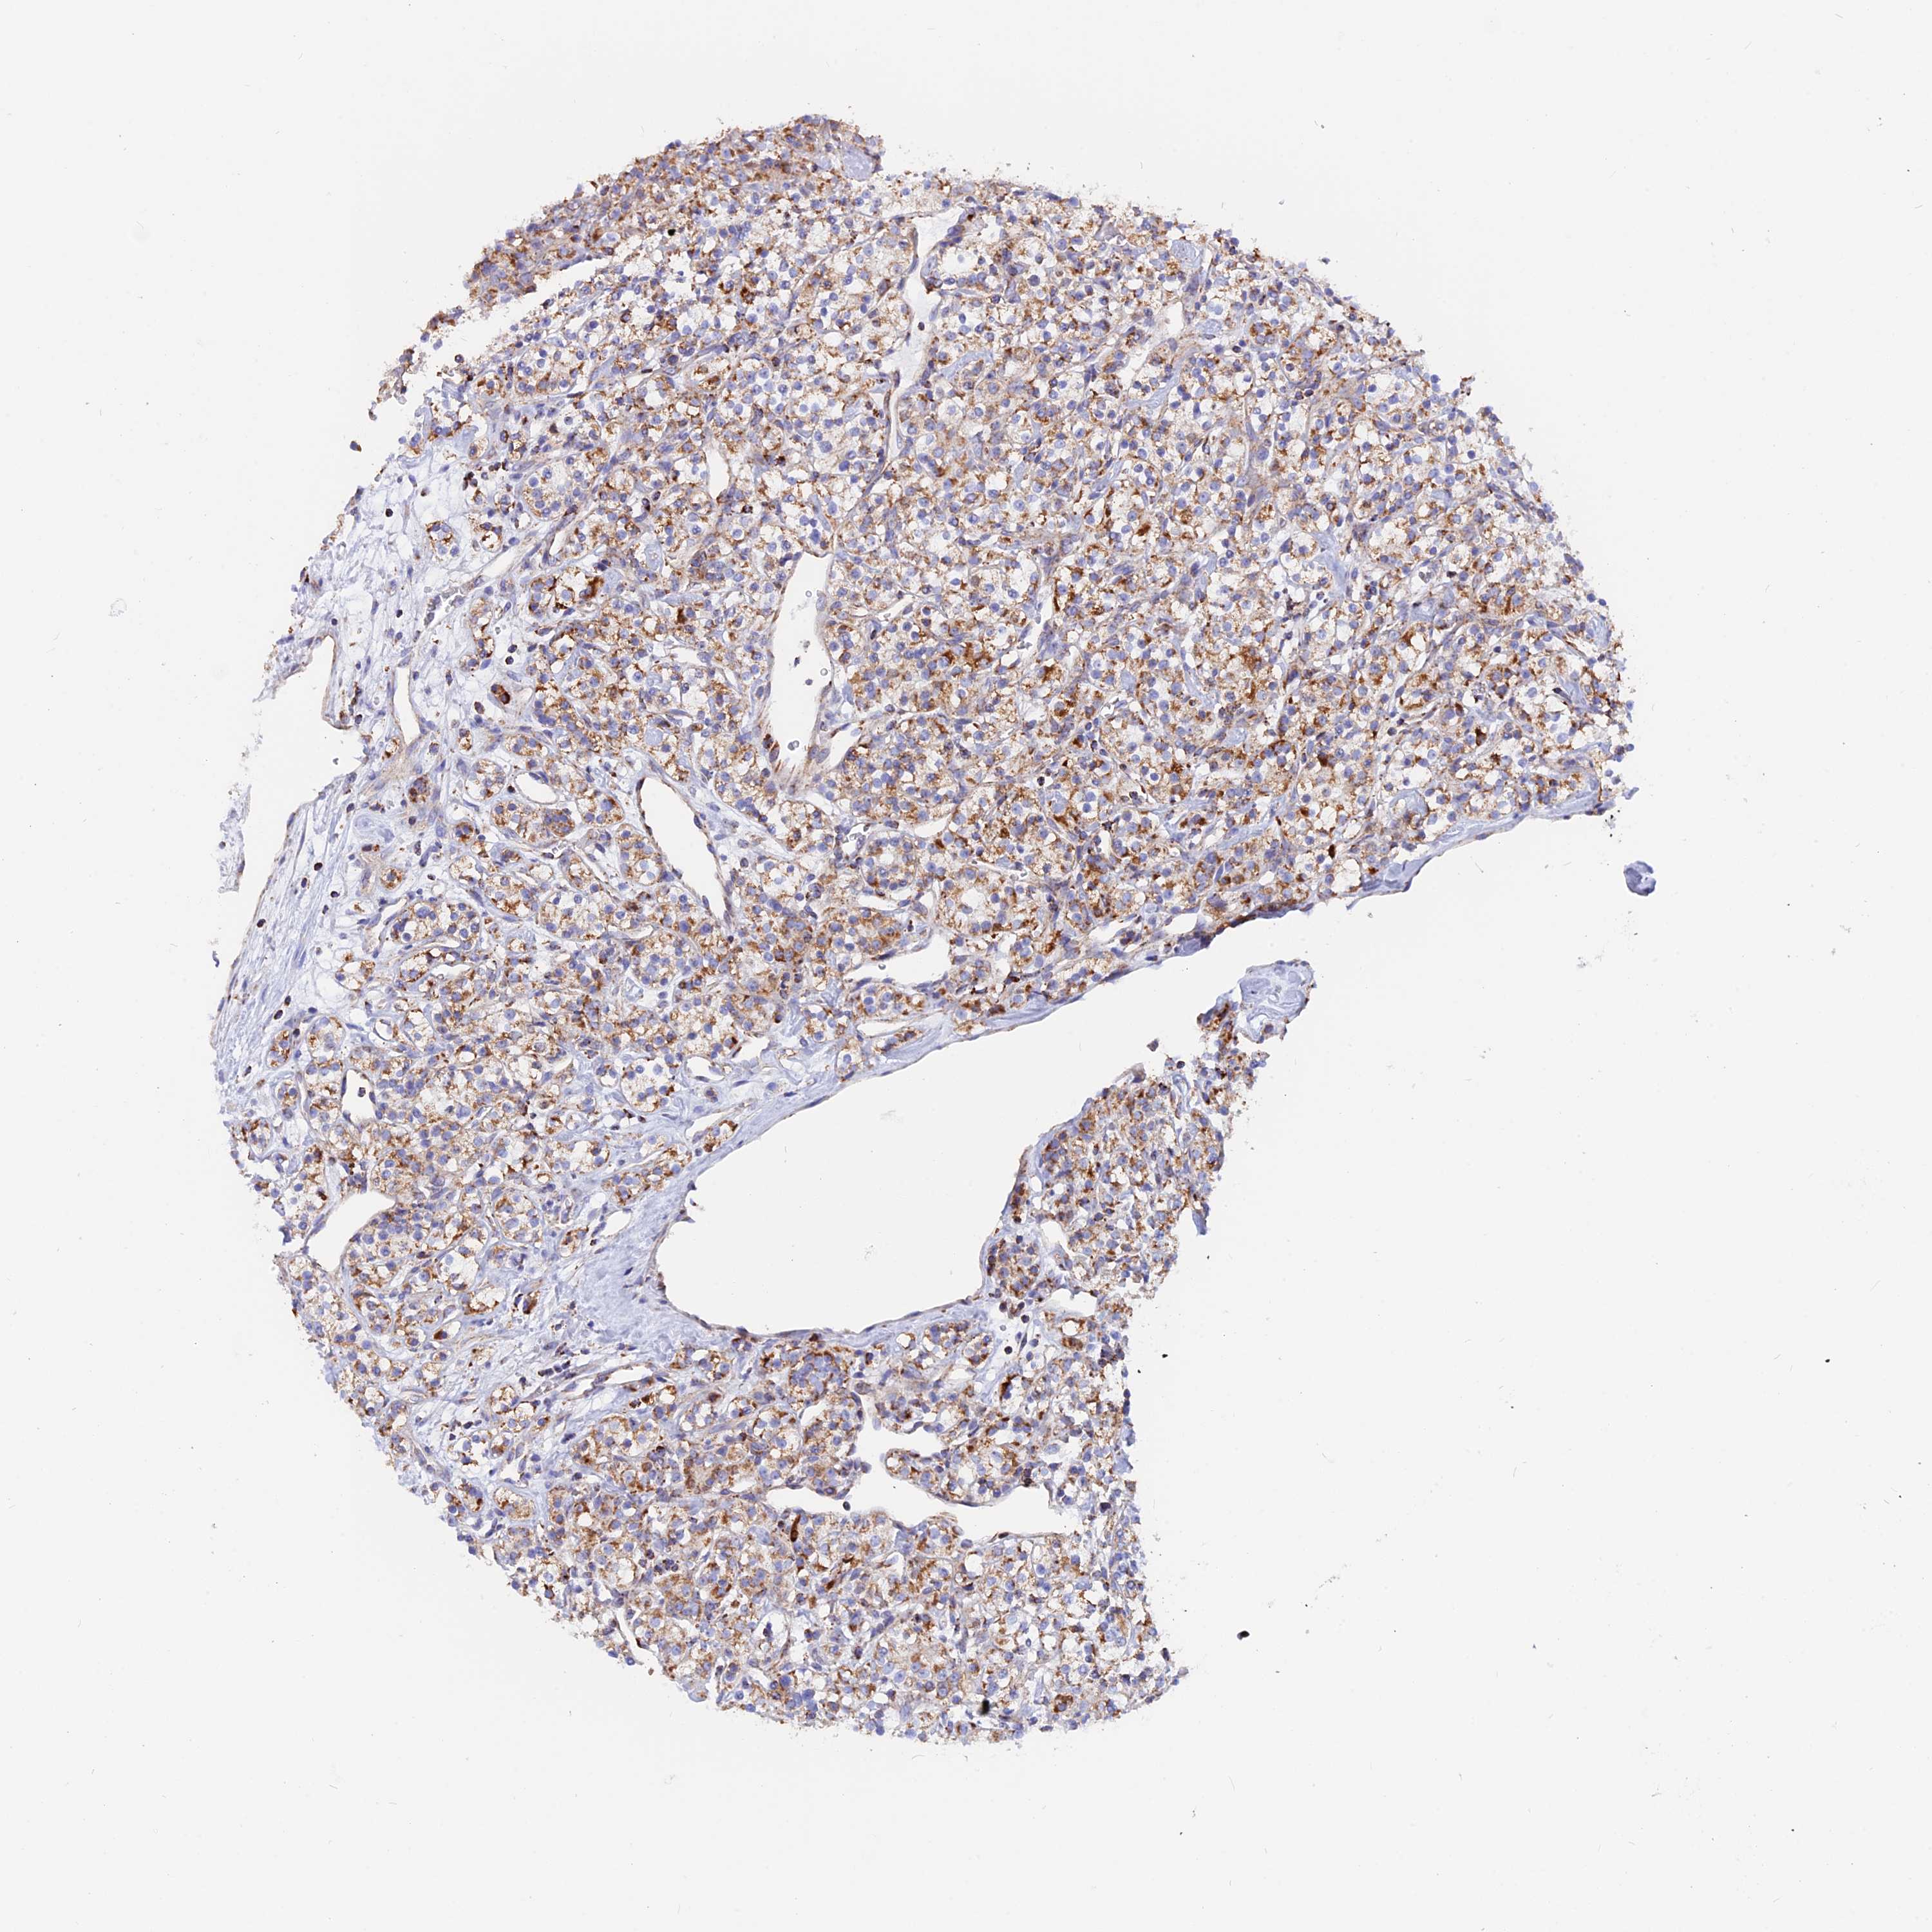

KIDNEY RENAL CLEAR CELL CARCINOMA (VALIDATION) - Interactive survival scatter ploti

The Survival Scatter plot shows the clinical status (i.e. dead or alive) for all individuals in the patient cohort, based on the same data that underlies the corresponding Kaplan-Meier plots. Patients that are alive at last time for follow-up are shown in blue and patients who have died during the study are shown in red.

The x-axis shows the expression levels (FPKM) of the investigated gene in the tumor tissue at the time of diagnosis. The y-axis shows the follow-up time after diagnosis (years). Both axes are complimented with kernel density curves demonstrating the data density over the axes. The top density plot shows the expression levels (FPKM) distribution among dead (red) and alive patients (blue). The right density plot shows the data density of the survived years of dead patients with high and low expression levels respectively, stratified using the cutoff indicated by the vertical dashed line through the Survival Scatter plot. This cutoff is automatically defined based on the FPKM cutoff that minimizes the p-score. The cutoff can be changed by dragging the vertical line or by entering a cutoff value in the square labeled "Current cut-off".

Under the Survival Scatter plot the p-score landscape (black curve; left axis) is shown together with dead median separation (red curve; right axis). Dead median separation is the difference in median mRNA expression between patients who have died with high and low expression, respectively. It is calculated as follows: median FPKM expression of dead patients with high expression - median FPKM expression of dead patients with low expression. This is intended to aid the user in visually exploring custom cutoffs and the associated p-scores and dead median separation.

Individual patient data is displayed and can be filtered by clicking on one or more of the category buttons on the top of the page. Categories describing expression level and patient information include: high, low, alive, dead, female, male and tumor stages. The scale of the x-axis can be toggled between linear and log-scale by clicking on the "x log" button. Mouse-over function shows TCGA ID, patient information and mRNA expression (FPKM) for each patient.

& Survival analysisi

Kaplan-Meier plots summarize results from analysis of correlation between mRNA expression level and patient survival. Patients were divided based on level of expression into one of the two groups "low" (under cut off) or "high" (over cut off). X-axis shows time for survival (years) and y-axis shows the probability of survival, where 1.0 corresponds to 100 percent.

GCDH is not prognostic in Kidney Renal Clear Cell Carcinoma (validation)

Best expression cut offi

Based on the FPKM value of each gene, patients were classified into two groups and association between prognosis (survival) and gene expression (FPKM) was examined. The best expression cut-off refers the FPKM value that yields maximal difference with regard to survival between the two groups at the lowest log-rank P-value. Best expression cut-off was selected based on survival analysis .

When clicking on this number, the vertical dashed line indicating cut-off, the interactive survival plot, and the Kaplan-Meier curve will be adjusted to show results based on the best expression cut-off.

: 13.71

P scorei

Log-rank P value for Kaplan-Meier plot showing results from analysis of correlation between mRNA expression level and patient survival.

N/A

TCGA RNA samplesi

RNA-seq data is reported as average FPKM (number Fragments Per Kilobase of exon per Million reads), generated by the The Cancer Genome Atlas (TCGA) .

Normal distribution across the dataset is visualized with box plots, shown as median and 25th and 75th percentiles. Points are displayed as outliers if they are above or below 1.5 times the interquartile range. FPKM values of the individual samples are presented next to the box plot.

Average pTPM 14.5

Number of samples 100